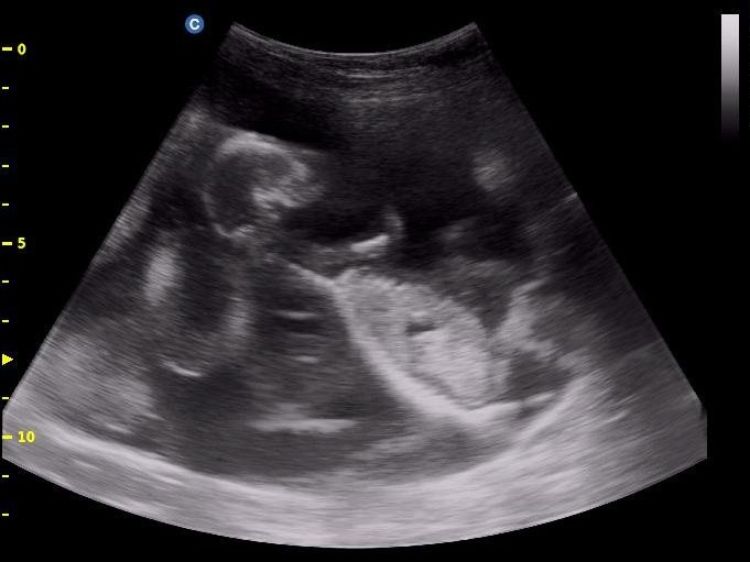

Transabdominal scanning of sheep and goats allows for a very efficient and accurate means of detecting pregnancy. Photo by Barbara Makela, Michigan State University Extension.

Transabdominal scanning of sheep and goats allows for a very efficient and accurate means of detecting pregnancy. The speed of scanning for experienced practitioners is largely a function of the efficiency of the animal handling system at a given farm. Speed and efficiency are also gained by use of an efficient means of applying lubricant (ultrasound gel) to the probe to allow for air-free skin contact, facilitating sound wave transmission. Experienced scanners with highly efficient handling systems can scan as many as 450 animals per hour at a 98% accuracy rate. The ideal window of pregnancy for transabdominal scanning is day 40-70. The most commonly used probes are variable frequency 3-5 mHz linear probes or 3 mHz sector scanning probes. Early pregnancy can be detected via transabdominal scanning using higher resolution units. However, the fetal compartment is small and easy to miss at this stage, hence the recommended minimum of 40 days. Producers interested in this application are advised to limit ram/buck exposure to no more than 2 estrus cycles (34 days in sheep and 42 days in goats) if a single scanning session is desired. Ideally, one would schedule scanning for 40 days following ram/buck removal. Pregnancy can also be detected with higher frequency probes (5-10 mHz) that are inserted in the rectum with a special, plastic extension tool. This allows placement of the probe closer to the gravid uterus, allowing visualization of pregnancy as early as day 18, with a conceptus size of less than 0.8 cm. The need for detection this early would likely be only in special cases when very early detection is desired and is not a general need.